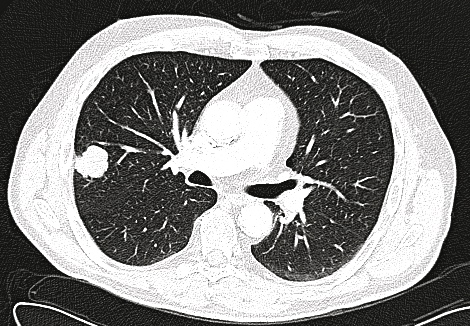

Image 1: Computed tomography showing the 3 x 2.8 cm lesion in the right upper lobe